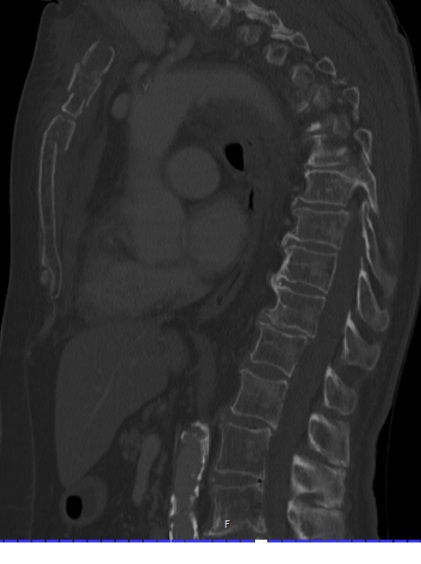

Fall from 4-meter height

Mechanism of injury: An 81 year old woman fell onto her back from a height of 4 meters. (Fig 6a-d) She sustained a multiple sternal fracture concomitant with a fracture of the 5th thoracic vertebra resulting in an unstable injury of the trunk. Fortunately she did not show any neurologic deficit or paraplegia.

Diagnosis: Complex sternal fracture with multidirectional instability (longitudinal fracture of the manubrium, transverse fracture involving 3 levels of manubrium and corpus sterni) Concomitant to this was a fracture of the 5th thoracic vertebra (AOB2.1).

Treatment: The sternal fracture has been managed by open-reduction and internal fixation with a locked plate osteosynthesis (MatrixRIB, I-Plate) through an anterior approach in the mid-line. b The thoracic spine has been managed employing dorsal instrumentation (internal fixator th4-th6).

Post-operative outcome: The wounds and bone healed uneventfully. Breathing was possible spontaneously without any restrictions. The patient reported on a significant reduction of the pain immediately after the operative procedure. Mobilization on the ward started on the first day after the procedure. No complications such as secondary failure, non-unions, pain or deformity of the chest wall could be seen during the follow up examinations of 6 and 12 weeks and 6 and 12 months.